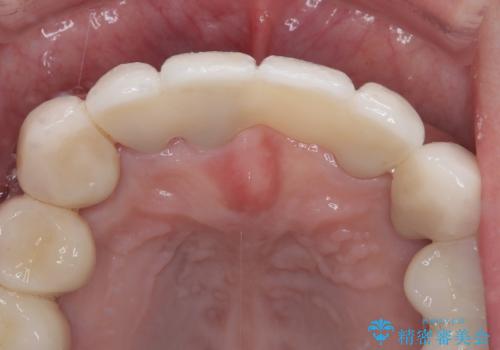

歯周病でグラグラの歯 矯正治療と歯周外科を併用した総合歯科治療

上顎口蓋からの堅い歯肉を移植する角化歯肉移植術を行いたかったのですが、体調不良から実施しなかったため、最終補綴物であるオールセラミッククラウンを装着した後に、知覚過敏や境目が見てしまうといった問題が一部で発生いたしました。

最終的には痛みや違和感のない状態にて治療を終えることができました。